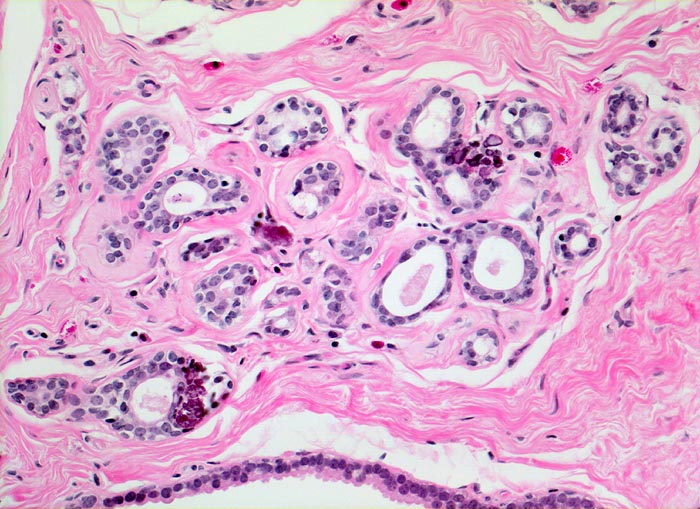

fibrös zystische Mastopathie mit Mikroverkalkungen

Fibrosiertes Läppchen mit Mikroverkalkungen.

Probeexzision wegen umschriebenen Mikroverkalkungen in der Screeningmammographie. Bei der Palpation lassen sich mehrere unscharf begrenzte derbe Knoten tasten.

Wenn auf der Mammographie bzw. auf dem Röntgenbild des Probeexzisates Mikroverkalkungen sichtbar sind, muss histologisch Mikrokalk nachgewiesen werden. Dies, um sicher zu gehen, dass die verdächtige Läsion histologisch erfasst wurde. Andernfalls müssen Stufenschnitte oder zusätzliches Gewebe untersucht werden, bis die Mikroverkalkungen histologisch nachgewiesen werden können.